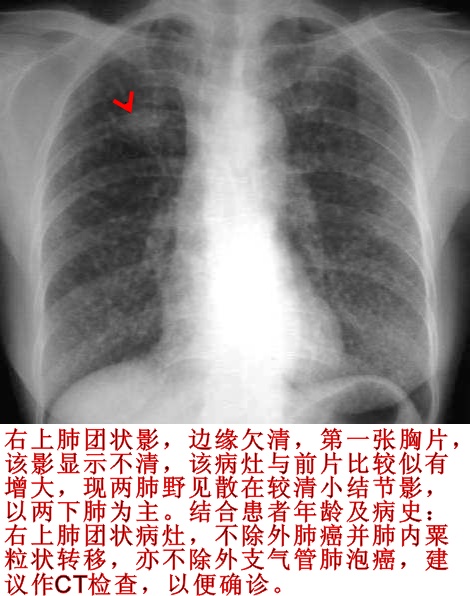

右肺上叶斑块状影,双肺弥漫分布多发小结节影,以双下肺叶为著。

考虑:1、右侧肺癌并双肺内血行转移。

2、肺泡细胞癌。

3、不除外血行播散型肺结核,建议结合临床查痰或做结核菌素实验。

右肺上叶类圆影,两肺小结节影,结合临床考虑右上肺癌伴肺内转移可能性大。

右上肺可见一团状软组织密度影,两肺散在粟粒状结节影,病变分布以两下肺为主,首先考虑肺泡癌,不除外血播行肺结核。

右肺第一前肋间见一结节影,边界欠请,两肺见散在的小结节影,以两下肺野明显,我考虑右上肺肺癌并肺内转移。